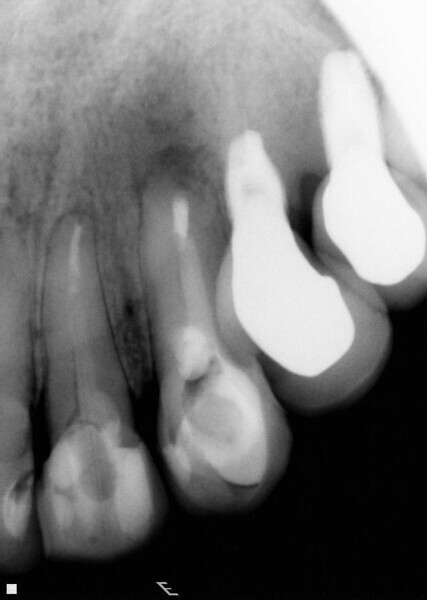

Fig. 5: Periapical radiographic follow-up after 30 and 90 days, showing a fast regression of the periapical lesion and a bone repair.

Fig. 6: Periapical radiographic follow-up after 30 and 90 days, showing a fast regression of the periapical lesion and a bone repair.